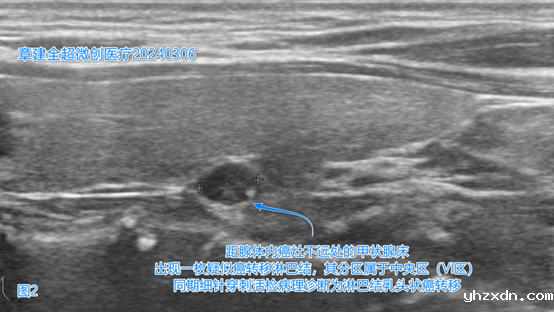

此外,在左侧甲状腺床(图2)、